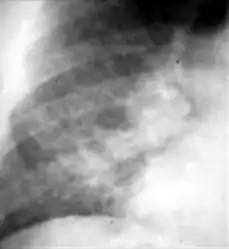

4. Pleural effusion - Presence of a significant amount of fluid within the pleural space. This finding must be distinguished from blunting of the costophrenic angle, which may or may not represent a small amount of fluid within the pleural space (except in children when even minor blunting must be considered a finding that can suggest active TB).

Chest x-ray showing dense opacity pleural effusion in the lower left lung of primary pulmonary TB.